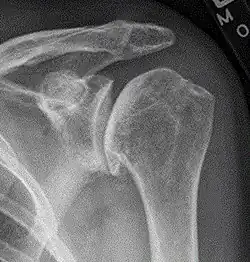

| Diagram of the human shoulder joint | |

The shoulder joint is composed of three bones: the clavicle (collarbone), the scapula (shoulder blade), and the humerus (upper arm bone) (see diagram). Two joints facilitate shoulder movement. The acromioclavicular (AC) joint is located between the acromion (part of the scapula that forms the highest point of the shoulder) and the clavicle. The glenohumeral joint, to which the term "shoulder joint" commonly refers, is a ball-and-socket joint that allows the arm to rotate in a circular fashion or to hinge out and up away from the body. The "ball" is the top, rounded portion of the upper arm bone or humerus; the "socket," or glenoid, is a dish-shaped part of the outer edge of the scapula into which the ball fits. Arm movement is further facilitated by the ability of the scapula itself to slide along the rib cage. The capsule is a soft tissue envelope that encircles the glenohumeral joint. It is lined by a thin, smooth synovial membrane.